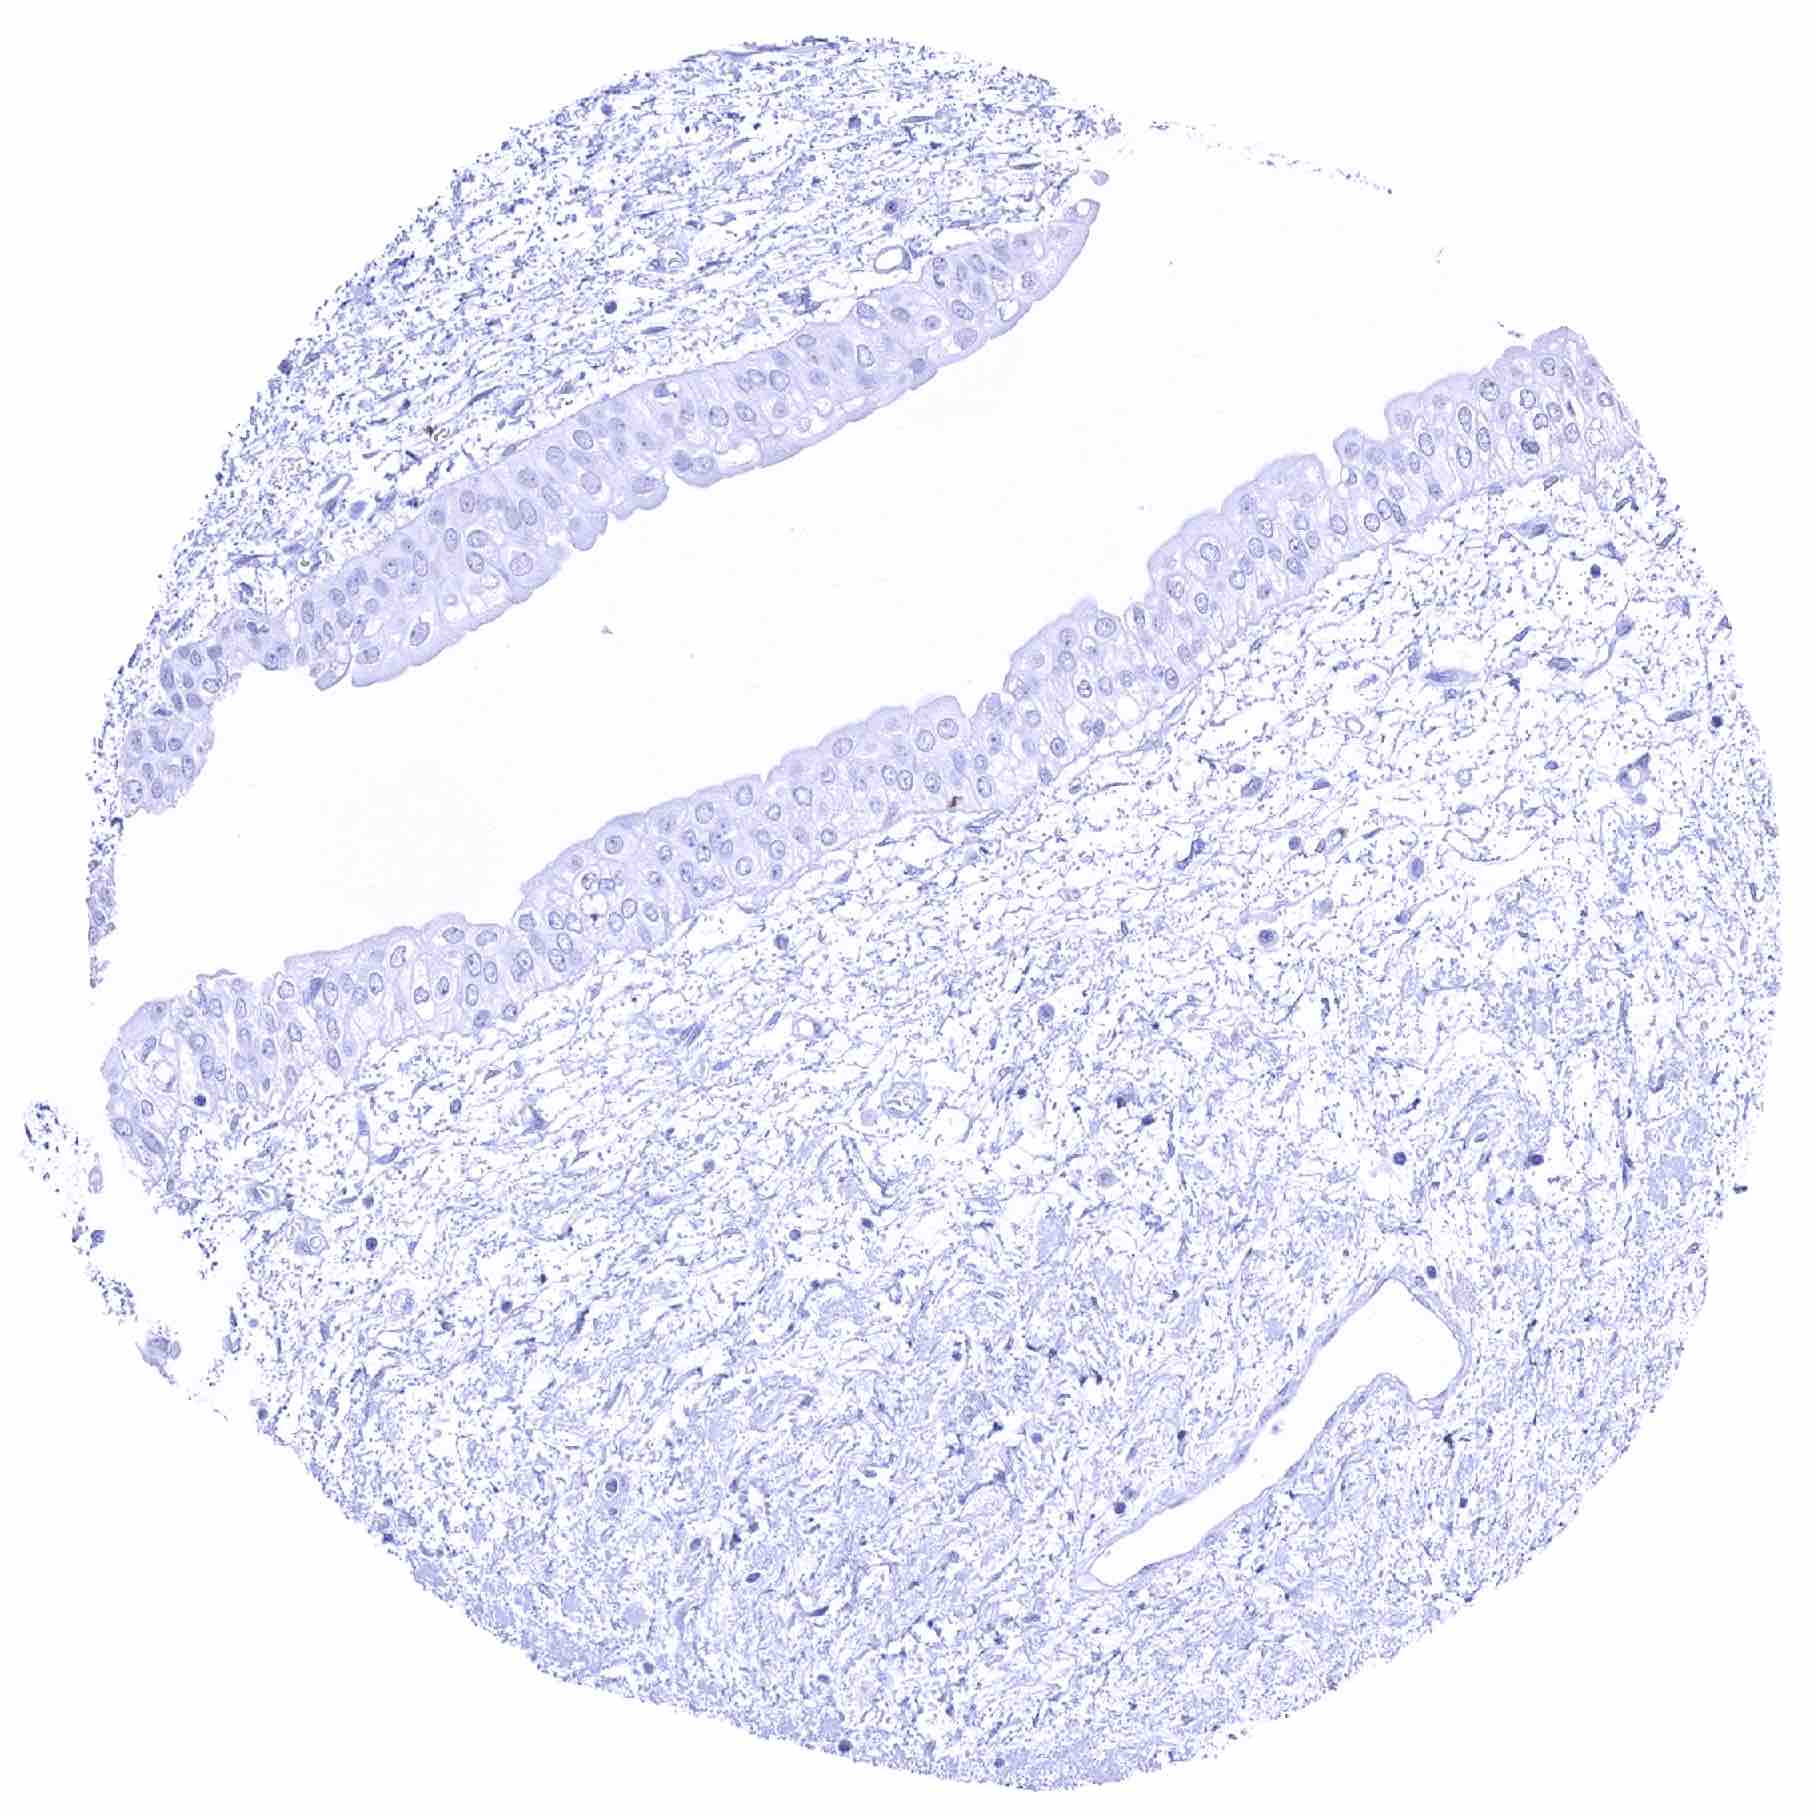

Uterus, ectocervix